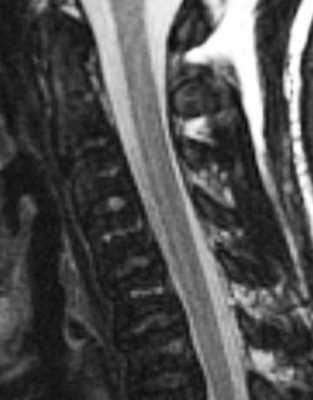

- Миелопролиферативные и миелодиспластические синдромы к которым относится хронический миелолейкоз и другие хронические лейкозы, полицитемия, мастоцитоз, эссенциальная тромбоцитопения при МРТ позвоночника проявляются однородно сниженным сигналом на Т1-взвешенных МРТ. На Т2-взвешенных МРТ позвоночника нередко наблюдается “обратная” яркость межпозвоночных дисков, они становятся светлее тел позвонков. МРТ головного мозга при опухолях кроветворной системы также может выявить его поражение.

МРТ позвоночника. Т2-взвешенная сагиттальная МРТ шейного отдела позвоночника. Хронический миелолейкоз.